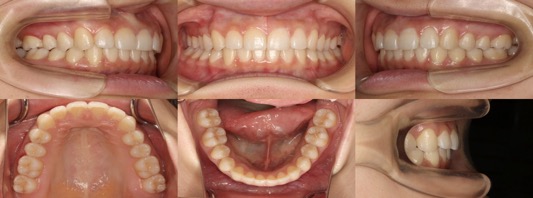

為您介紹隱適美矯正的治療案例。

※案例圖片著作權:隱適美醫師網(禁止轉載)

從案例照片的矯正前後對比中,可以清楚地看出其效果。